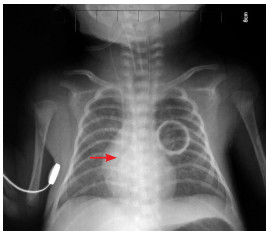

X线定位法判断标准:患儿仰卧位行胸片检查,PICC尖端应位于上腔静脉中下1/3段或上腔静脉与右心房交界处,胸片显示导管尖端位于第5~7胸椎,即为正常位置,见图 2。

图 2 理想的PICC置管位置 导管尖端位于上腔静脉中下1/3段,约平第6胸椎(箭头所示)。 |